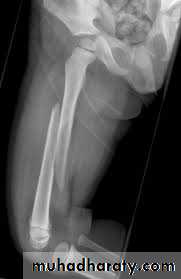

Femoral shaft fracture

This fracture occurs at any age, it is common especially in young adults, and usually results from a high energy injury, such as

( car accident , fall from height).

Fracture may be

spiral,

transverse, comminuted, pathological,

or compound.

Most fractures have some degrees of comminuation (small fragment, single large butter fly, extensive comminuation).

X-ray :

Shows the type of fractures, and displacement. The x-ray should include the hip and knee and x-ray of pelvis to avoid missing segmental fractures, knee injuries, fractures of neck of femur, dislocation of hip, fractures of acetabulum and pelvis.